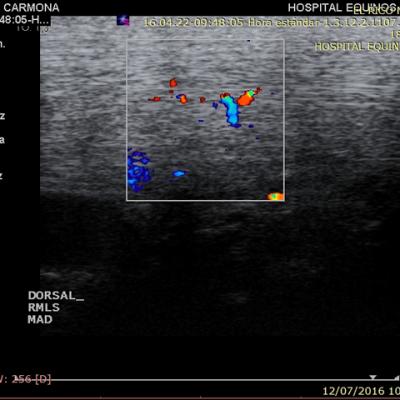

Diagnóstico por imágenes

Las imágenes médicas permiten, gracias a la posibilidad de visualizar estructuras internas, un diagnóstico más certero. Sin embargo estas no son mágicas, requieren de un clínico capacitado tanto en la obtención como la interpretación de las mismas, junto con la decisión de qué tipo de imagen debe obtenerse, basándose en un examen clínico especializado, para así colaborar con las finanzas del cliente.